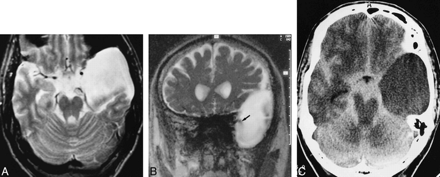

44-year-old man with left-sided tinnitus and hearing loss, paraesthesia, and respiratory distress.

A, T1-weighted transverse image (500/12/2) of the posterior fossa shows a paramedullary, space-occupying lesion with signal intensity similar to CSF, compressing the left ventrolateral portion of the medulla oblongata (arrow).

B, T2-weighted SE image (2000/80/1) of the same section as in A. Different compartments are not visible; the lesion has the same signal intensity as the surrounding CSF spaces, and margins of the cyst are not reliably detectable, making the diagnosis of an arachnoidal cyst highly probable.

C, Corresponding preoperative SSFP image (20/25/1) shows a circumscribed, hyperintense, premedullary lesion (large arrow), indicating stationary CSF of a noncommunicating arachnoid cyst in contrast to the significantly reduced signal of moving CSF in neighboring compartments (small arrows) and in the fourth ventricle (arrowhead). This finding strongly supports the decision for neurosurgical intervention.

D, SSFP image (20/25/1) after membranectomy shows signal attenuation in most parts of the formerly hyperintense cyst (arrow), indicating communication with neighboring CSF spaces. The patient experienced relief of his symptoms.